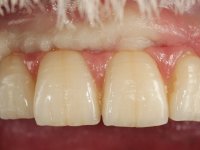

Segunda Fase

6 meses após a colocação da ponte, o paciente sofre um novo traumatismo comprometendo a viabilidade dos dentes 1.2 e 1.1. Foi realizada uma prótese removível acrílica para reabilitar provisoriamente o paciente enquanto foram extraídos os dentes 1.2 e 1.1 e foi colocado o implante no local do dente 1.1. Passados 3 meses foi realizada uma impressão ao implante colocado no 1.1 e simultaneamente foi feito um arrasto da ponte dos dentes 2.1 e 2.2. Para esse efeito no implante 2.1 foi utilizado um parafuso de uma peça de transferência. Dessa forma conseguiu-se impressionar corretamente a arquitetura gengival do sector antero-superior. O objetivo era simultaneamente impressionar corretamente esta zona e aproveitar a estrutura metálica desta ponte para confecionar a nova ponte de 4 elementos. Foi colocado um parafuso de cicatrização no implante 2.1 e foram acrescentados os dentes 2.1 e 2.2 na prótese removível. Com perícia laboratorial foi criada uma nova infraestrutura metálica de 4 elementos assente nos implantes 1.1 e 2.1 e com os elementos pônticos suspensos 1.2 e 2.2. No implante 2.1 manteve-se a conexão interna ao implante no implante 1.1 optou-se por uma peça intermédia facilitando a inserção da infraestrutura. A nova infraestrutura foi verificada em boca. Como pode ter havido alguma alteração da arquitetura gengival com a remoção da ponte e colocação do parafuso de cicatrização no 2.1, foi feita uma chave de silicone para permitir uma impressão de arrasto da infraestrutura metálica. Uma nova gengiva artificial foi realizada no modelo de trabalho de acordo com esta impressão de arrasto. Foi colocada cerâmica de tonalidade coronária e gengival. A peça protética foi aparafusada lentamente em boca para permitir uma adaptação dos tecidos moles. Após o correto assentamento e verificação imagiológica a ponte foi definitivamente apertada em boca e os orifícios de acesso obturados. Independentemente dos infortúnios que o paciente teve, pude ter a satisfação de o ver contente com esta reabilitação.